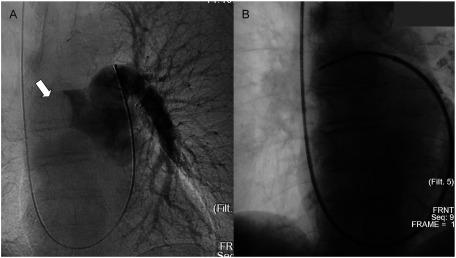

Endovascular Catheter Biopsy for the Diagnosis of Pulmonary Artery Sarcoma.

The diagnosis of pulmonary artery sarcoma (PAS) is challenging, and its definitive diagnosis is mainly confirmed using specimens obtained during surgery or autopsy. Endovascular catheter biopsy was performed in five patients with suspected PAS to establish a definitive diagnosis. Aspiration biopsy was performed in all patients, and forceps biopsy was performed in one patient. Three patients were diagnosed with PAS, and no definitive diagnosis was obtained in two patients with squamous cell lung carcinoma with pulmonary artery infiltration. Endovascular catheter biopsy is helpful in the diagnosis of PAS and should be performed when a tumor is suspected.

肺动脉肉瘤(PAS)的诊断具有挑战性,其确诊主要通过手术或尸检获取的标本得以证实。对5例疑似PAS的患者进行了血管内导管活检以明确诊断。所有患者均进行了抽吸活检,1例患者进行了钳取活检。3例患者被诊断为PAS,2例伴有肺动脉浸润的肺鳞状细胞癌患者未获得明确诊断。血管内导管活检有助于PAS的诊断,当怀疑有肿瘤时应进行该检查。